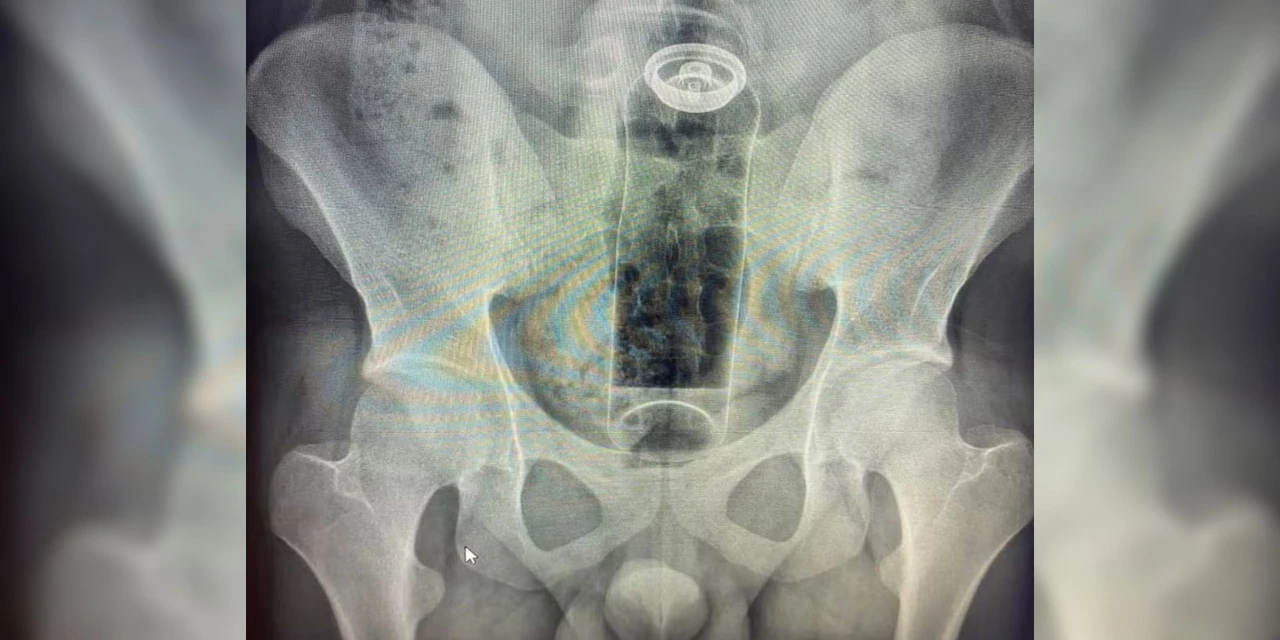

Um caso recente envolvendo um jovem de 19 anos, internado para a retirada de um frasco de desodorante do reto, motivou um importante alerta da comunidade médica. O episódio, ocorrido durante uma exploração sexual, destaca os perigos da introdução de objetos não apropriados no corpo, prática que pode levar a cirurgias complexas, infecções generalizadas e até ao óbito.

No caso do jovem de 19 anos, a embalagem subiu para o reto e não pôde ser removida sem intervenção hospitalar.

Especialistas explicam que a anatomia da região favorece acidentes quando não há o uso de acessórios corretos. O intestino realiza movimentos peristálticos (contrações involuntárias) que, somados ao vácuo criado na região do reto, podem "sugar" o objeto para o interior do corpo rapidamente.